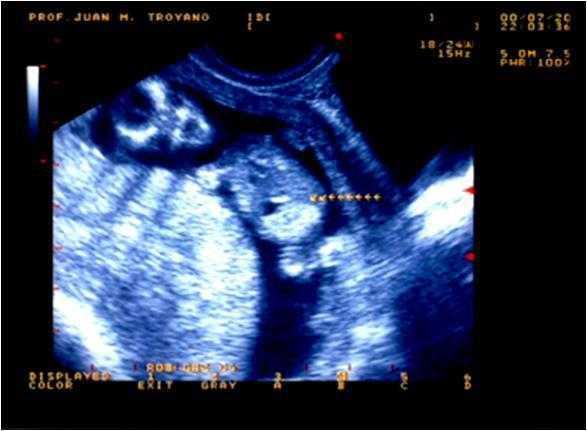

Hemos tenido la oportunidad de estudiar un niño que, actualmente, tiene 3 años de edad. Fue remitido por su pediatra a los 5 meses de vida tras un episodio de hematuria macroscópica, en el que se objetivó la presencia de un cálculo en el pañal. Se trata del primer hijo de unos padres no consanguíneos, sin patología previa de interés y con antecedentes de miembros con cólicos nefríticos en la rama paterna. Durante la gestación se detectaron en los controles ecográficos fetales una hiperecogenicidad del colon en ausencia de otras anomalías intestinales (figura 1 y figura 2) y una luminiscencia nucal discretamente aumentada, sin otros hallazgos de interés. Por este motivo, al nacimiento se realizó un test del sudor para descartar la presencia de fibrosis quística, cuyo resultado fue normal.

Describimos de esta forma un caso de cistinuria de presentación clínica temprana, reflejo de la gran capacidad litogénica que posee esta entidad, con la particularidad del hallazgo ecográfico prenatal de hiperecogenicidad del colon secundaria al depósito de cristales de cistina en dicha localización. Esta forma de presentación de la cistinuria fue descrita en 20063 y confirmada posteriormente4. La explicación de este hallazgo radica en que los cristales de cistina se forman intraútero en el riñón fetal, pasan al líquido amniótico y, posteriormente, son deglutidos. El hallazgo ecográfico de la hiperecogenicidad intestinal intraútero ha sido relacionado clásicamente con la fibrosis quística, motivo por el que se realizaron los estudios necesarios para descartar esta enfermedad al nacimiento de nuestro paciente. Su negatividad y la clínica tan precoz permitieron el diagnóstico. El conocimiento de esta asociación puede conducir al diagnóstico precoz de la enfermedad, lo que permitirá establecer un tratamiento adecuado.

Figura 1. Hiperecogenicidad intestinal, con densidad sónica semejante al hueso fetal.